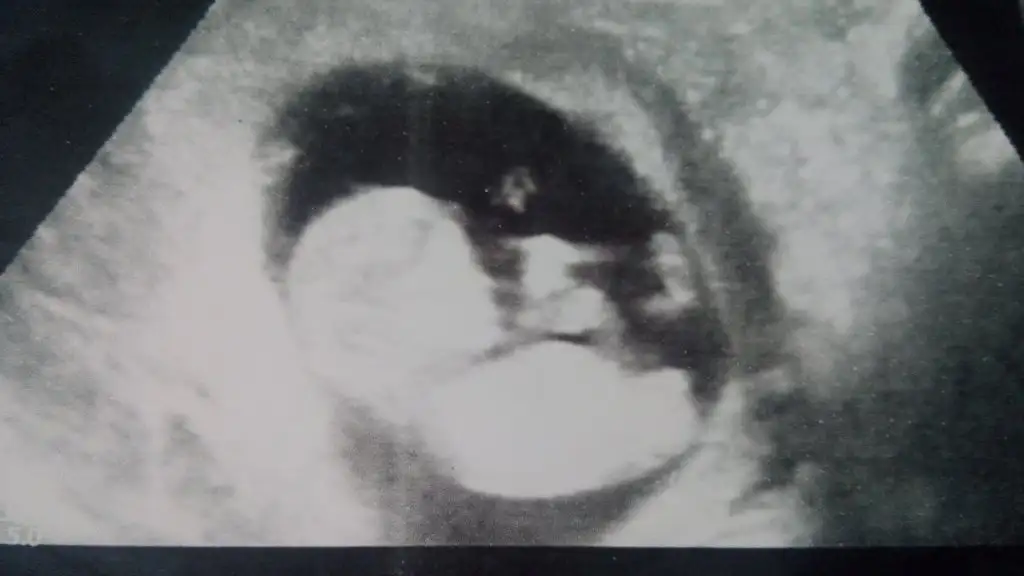

dr soylemeden siz gorun genital nub teorisi ( bebegin cinsiyeti)

Bu bebiste erkek gibi geldi bana dikkatli bakinca cikinti var yukari kalkik paralel deil.. kac hagtalik sen ne hissediyorsun ??? Doktor hicmi yorum yapmadi

Canim erkek bebekte genelde net konusurlar kiz bebekte ikilem oluyo bacak arasi bos yorum yapamiyolae kiz netlik kazanmiyo :(( malesef ben cok ugrastim netlesmedi kiz dedim birakyim :))